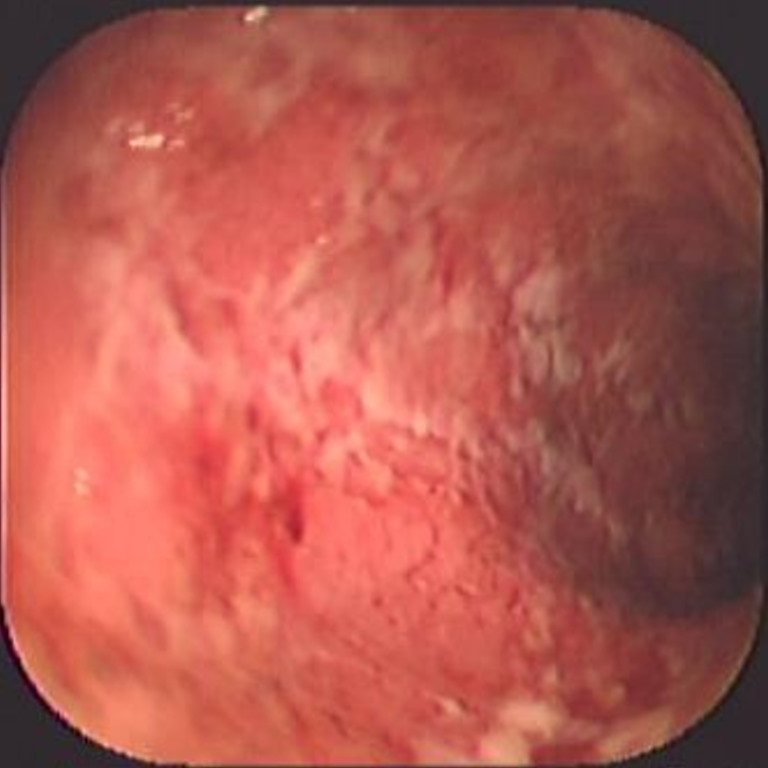

Colitis ulcerosa crónica inespecífica

Envíado por Dr. Carlos Ernesto Arévalo